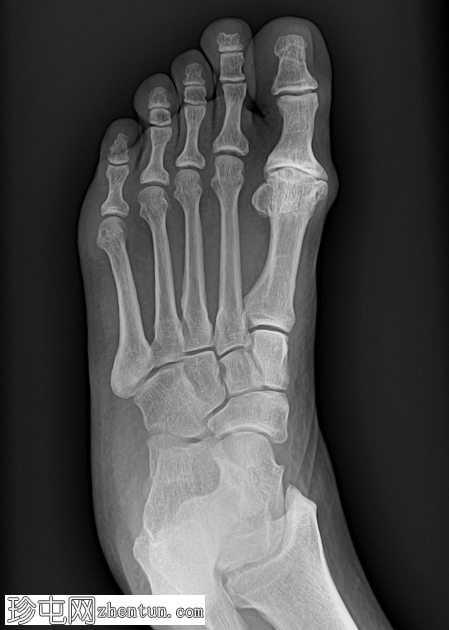

X线片

斜位

第一跖趾关节可见巨大骨赘,关节间隙变窄。

斜位片能更清晰地显示关节间隙变窄。

第一跖骨头背侧可见巨大骨赘。

拇外翻是足部最常见的骨关节炎类型。

拇外翻的特征是骨赘形成和关节僵硬,并伴有第一跖趾关节背屈进行性受限。

拇外翻可采用 Coughlin 和 Shurnas 分级法进行分级:

1 级:轻度关节间隙狭窄

2 级:中度关节间隙狭窄伴骨赘形成

3 级:重度关节间隙狭窄伴广泛骨赘形成

4 级:与 3 级相同,但在被动背屈中段出现疼痛

本病例被归类为 Shurnas 4 级。